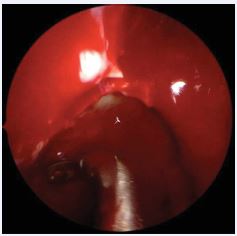

Next, the diseased mucosa of the anterior and posterior ethmoids must be removed, including lamina papyracea, skull base, and lateral face (and anterior portion, when necessary) of the middle turbinate (Figure 4).

Figure 4 Removal of diseased mucosal tissue from the right ethmoid sinus using blunt, curved, atraumatic suction instruments.